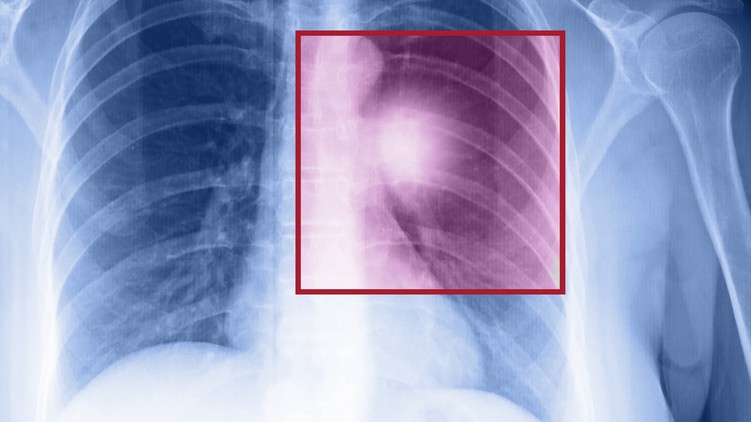

Alacsony sugárterhelésű CT-vizsgálat a leghatékonyabb módszer a tüdőrák szűrésére

- Az alacsony sugárterhelésű tüdő CT-vizsgálatok igen részletes képet nyújtanak a tüdő állapotáról. A modern szoftverek segítségével a tapasztalt radiológusok akár pár milliméter nagyságú elváltozást is képesek felfedezni a tüdőben, ezek sebészeti kezelése pedig hatékonyan megoldható. Ennek tükrében a tüdőrákszűrő vizsgálatok szerepe felértékelődik." – fejtette ki Dr. Kardos Lilla, az Affidea Magyarország vezető orvosigazgatója.

Fontos, hogy a betegség szűrése alacsony sugárterhelésű tüdő CT-vizsgálattal történjen, hiszen a klasszikus mellkas röntgenvizsgálat az eseteket nagy részében nem ad megfelelő képet az elváltozások biztos felismeréséhez. Sokakban felvetődik a kérdés, hogy mennyire kockázatosak ezek a tüdő CT vizsgálatok, hiszen a computer tomográfia (CT) röntgensugarat használ, amely szintén rákkeltő lehet.

- Ma már egy alacsony sugárterhelésű tüdő CT-vizsgálat sugárterhelése nem több, mint amennyi háttérsugárzás éri a szervezetet egy tengerentúli repülőút alatt. Tehát egy tüdőrákszűrő CT-vizsgálat haszna jóval meghaladja annak kockázatát. Évek óta dolgozunk azon, hogy a CT-vizsgálatoknál a lehető legkisebb sugárterhelés érje a páciensek szervezetét, ugyanakkor a képek minősége a lehető legjobb legyen. Ezt a sugárdózis-csökkentő tevékenységünket az Európai Radiológus Társaság ötcsillagos minősítéssel ismerte el – tette hozzá Dr. Kardos Lilla.